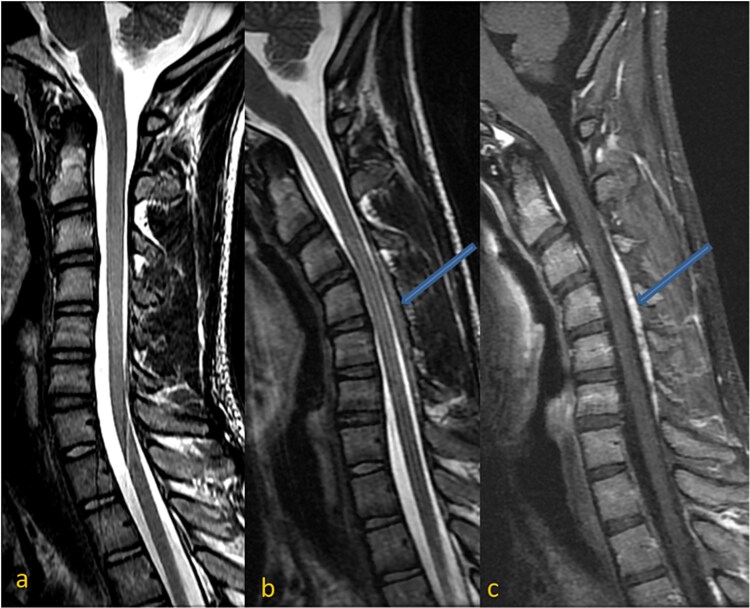

平山病(Hirayama disease, HD)是一种罕见的颈椎脊髓病,累及下颈肌瘤,引起不对称或单侧上肢远端肌肉萎缩。诊断依赖于临床表现、神经传导研究和颈椎中性位和屈曲位的MRI。我们提出一个17岁的男性无痛,进行性无力和萎缩的左前臂和手的肌肉,并伴有多汗症。最初的颈椎MRI显示颈椎前凸消失,下颈半索萎缩,前角细胞T2信号强度增加。屈曲MRI显示后硬脑膜前移,颈髓受压,静脉丛充血,后硬膜外间隙扩大并增强,证实平山病。在常规MRI检查中出现颈髓萎缩和不对称扁平的青少年男性,应怀疑为平山病。屈曲MRI对识别硬脑膜前移位及相关改变至关重要,确保准确诊断。

Hirayama disease (HD) is a rare cervical myelopathy involving lower cervical myotomes, causing asymmetric or unilateral distal upper extremity muscle atrophy. Diagnosis relies on clinical findings, nerve conduction studies, and cervical spine MRI in neutral and flexion positions. We present a 17-year-old male with painless, progressive weakness and atrophy of the left forearm and hand muscles, along with hyperhidrosis. Initial cervical spine MRI revealed loss of cervical lordosis, lower cervical hemicord atrophy, and increased T2 signal intensity in the anterior horn cells. Flexion MRI demonstrated anterior shifting of the posterior dura, cervical cord compression, venous plexus congestion, and posterior epidural space widening with enhancement, confirming Hirayama disease. In adolescent males with cervical cord atrophy and asymmetric flattening on routine MRI, Hirayama disease should be suspected. Flexion MRI is crucial for identifying anterior dural shifting and related changes, ensuring accurate diagnosis.